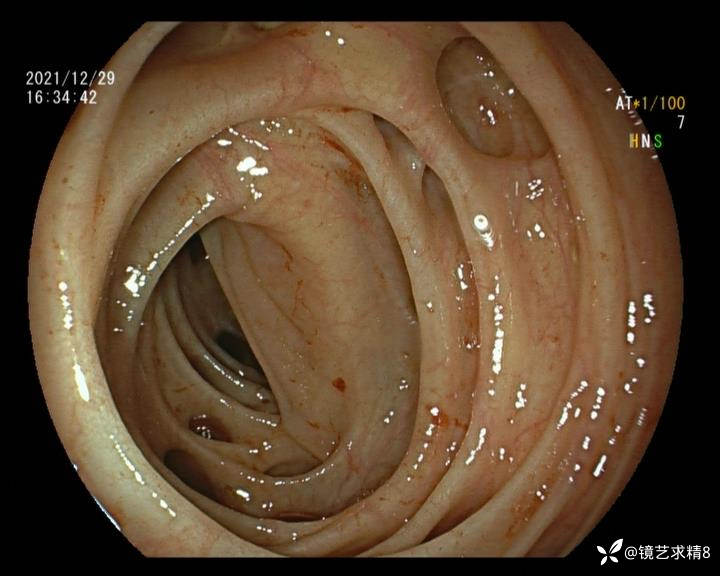

结肠内违建⥤结肠多发憩室☞续

小壮兵爱学习等 2人推荐看到手机存有2年前一个病例仅有的3张图片,因为没有更多的图片就只描述了多发憩室这个内容,没想到浏览量很快上万,很多都和我一样第一次见这么多憩室的结肠,就不得不想要把2年前所有的片子拷贝出来分享。该病例憩室合并外源性因素成为憩室出血的原因。后面附有代表性的全结肠图片。

患者以消化道出血入院,胃镜未见异常,肠镜进入乙状结肠就看到很多憩室,同时还看到肠腔用清肠药后移动下来1枚尖锐的枣核,这么多憩室,这个枣核扎入憩室的机会非常大,推测应该是掉入一坑🕳就算出来还会有很多坑🕳🕳🕳等着,掉入憩室内很容易刺破血管,这可能就是消化道出血的原因,继续前进可以看到有一些憩室内翻,还有一些息肉,问题来了,那么多憩室,犯罪分子是抓住了,它在那些憩室内作过案?到达回盲部后挨个冲洗,但憩室大小又不足以把镜头进入憩室内观察,针对有血块的憩室冲洗后可疑出血的以夹子闭合或套扎,取出枣核,如果有锥形透明帽可能钻入憩室精准电凝效果更好,若内镜下操作失败介入治疗成功率更高,经内镜下治疗后观察未再出血出院。